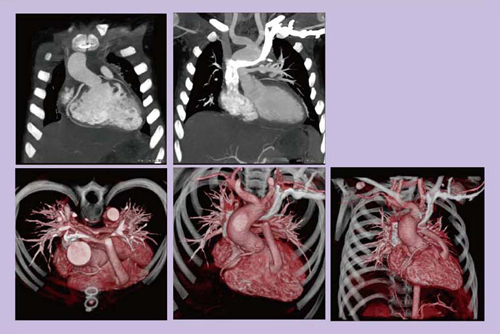

図6は,超音波検査で左房粘液腫が疑われた症例で,緊急手術となったため,外科からの依頼で術前に冠動脈評価を行った。粘液腫が嵌頓しそうになっており,周辺にもかなり侵襲していることがわかる。血管成分も多く,悪性が強く疑われた。動画もスムーズに観察することが可能であり,形態から血管成分も含めた腫瘍の性状まで評価できるため,CTのみで外科医に対して十分に有用な情報を提供できる。

図6 47歳,男性,心臓腫瘍

図7は,2歳,男児,巨大側副血行路(MAPCA)の症例である。鎮静剤および息止めなしの心電非同期で,スキャンタイム0.27秒,被ばく線量1.17mSvで撮影可能であった。小児の場合,従来の16スライスCTでは,医師数人がかりで患者を鎮静させ,呼吸状態に注意を払いながら検査を行う必要があり,検査時間も長くて大変であった。しかし,Definition Flashでは,軽い鎮静のみで息止めが不要になり,検査の省力化と効率化につながっている。

図7 2歳,男児,MAPCA(鎮静剤・息止めなし)

図8は,4歳,男児,心室中隔欠損・肺動脈閉鎖症の術後症例である。鎮静を軽くかけ,息止めなしで撮影し,スキャンタイム0.42秒,被ばく線量1.33mSvであった。小児外科からの要望であった冠動脈も,おおむね描出できている。

図8 4歳,男児,心室中隔欠損・肺動脈閉鎖症術後